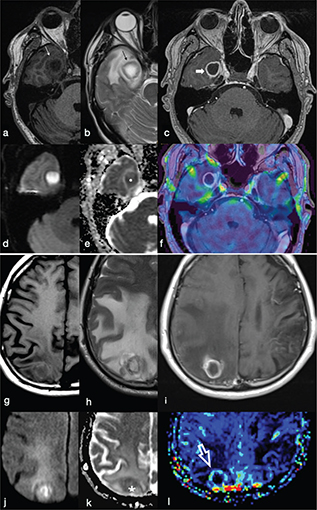

FIG 11. Differences between a Pyogenic Brain Abscess (a-f) and a Hypercellular Lung Metastasis (g-l). The peripheral ring of the abscess and cystic metastasis are hyperintense on T1w (a, g), hypointense on T2w (b, h) and show complete rim enhancement on T1w+Gd (c, i) images. The core of the lesion is hypointense on T1w (a, g), hyperintense on T2w (b, h) and may show restricted diffusion on DWI (d, j) and ADC maps (e, k). However, dynamic susceptibility contrast enhanced PWI does not show evidence of increased relative cerebral blood volume (rCBV) in the gadolinium-enhancing rim of the abscess (f) in comparison to the increased perfusion of the enhancing rim appreciable in the metastasis (white open arrow in l).

PWI provides information about the vascularisation of a lesion. Usually, PWI in pyogenic BA demonstrate low relative cerebral blood volume (rCBV) in the capsule, whereas necrotic brain tumours show elevated rCBV as a result of neoangiogenesis within the tumour tissue (Figure 11).11 This technique may be useful in the differential diagnosis of ring-like enhancing brain lesions that may mimic BA. These include neoplastic lesions (glioblastoma, metastases) and demyelinating lesions. However, rCBV values may vary according to the stage of the capsule: higher in the early stage than in the late stage in which the fibroblasts are dominant.5,11